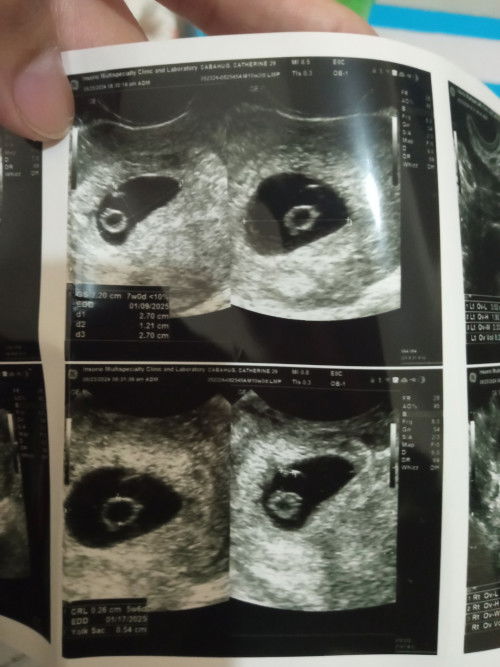

Magbasa pabalik ko po after 7days para macheck kung my heartbeat na si baby..

antay ng 7 days para macheck kung may heartbeat na

Repeat scan after 7 days daw po.